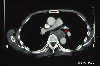

CT

A case of type Ip+IIc carcinosarcoma of the esophagus with minute invasion to the submucosa.

Detailed data.